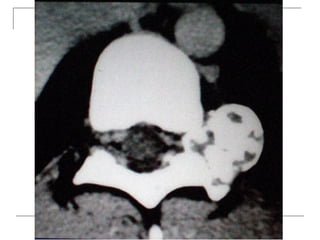

CT Scan

       better visualization of bone pathology (eg.

cortical destruction)

     fracture

     tumor

CT Scan  better visualization of bone pathology (eg. cortical destruction)  fracture  tumor